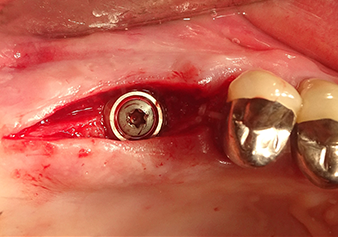

The Schneiderian membrane is carefully detached with the Z25P instrument (phase 1)

Fig.3: Following marking of the implant position and initial expansion of the bed, the Schneiderian membrane is carefully detached with the Z25P instrument (phase 1).